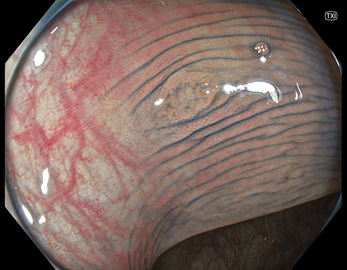

特に、下のような「Ub型(全く凸凹の無い完全に平坦な病変)」は、以前は「ほとんど見つからなかった」のが、TXIを使うようになってから「日常的に」見つかるようになりました。

通常観察 TXIモード

青い色素は追加していません![]()